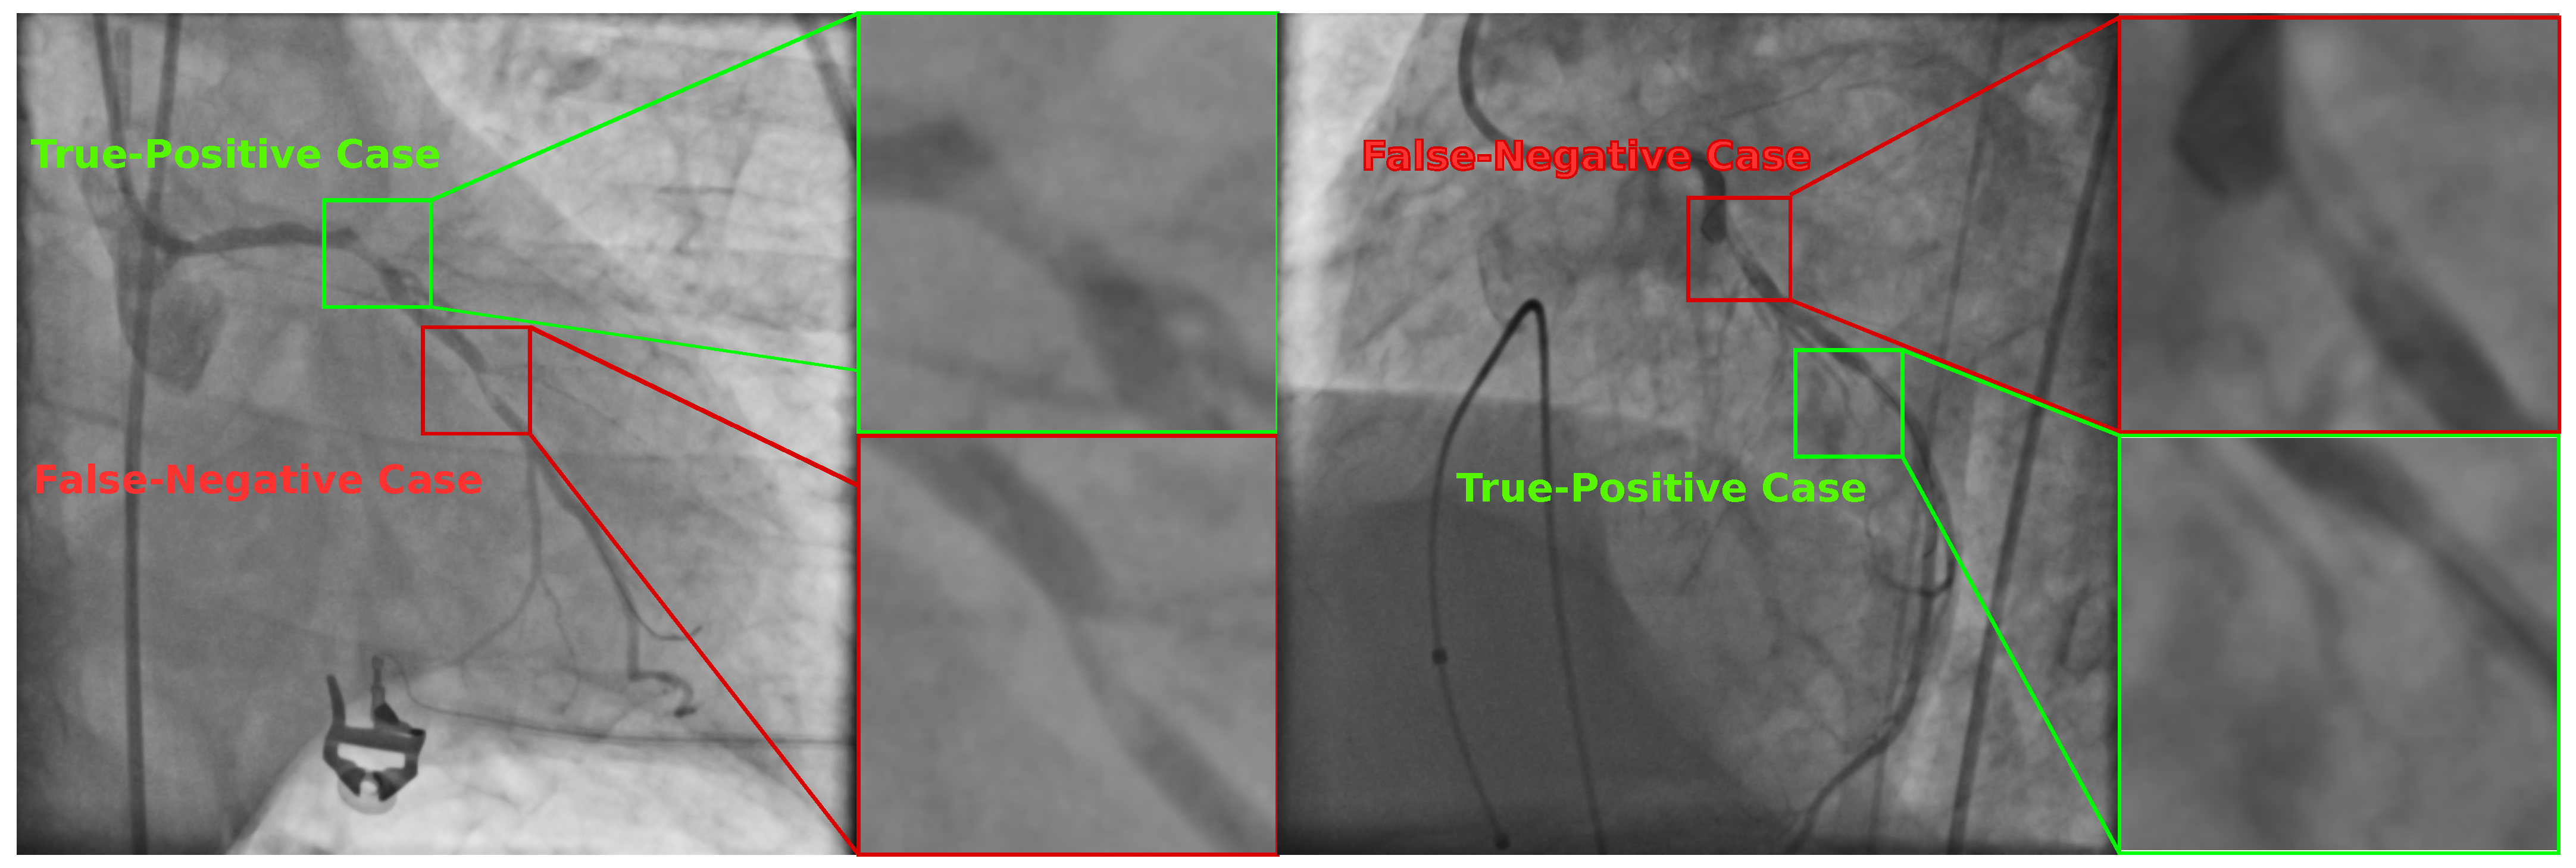

In order to illustrate the detection of coronary stenosis in X-ray images, Figure 5 illustrates two selected angiograms with certain zones classified as positive stenosis cases by the SVM-based classifier. However, only two of them were classified correctly. The other two instances are non-stenosis regions according to the specialist.

Figure 5.

Selected X-ray angiograms with True-Positive and False-Positive stenosis cases detected by the SVM-based classifier using the set with 20 features found by UMDA.

Figure 6 illustrates two selected angiograms which include correct and incorrect classification results. In the first scenario, the classifier failed to detect positive stenosis cases since it labeled regions as negative when there were present stenosis cases. The remaining labeled cases were classified in a correct way.

Figure 6.

Selected X-ray angiograms with True-Positive and False-Negative stenosis cases detected by the SVM-based classifier using the set with 20 features found by UMDA.